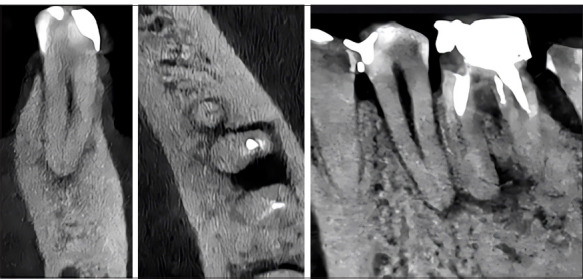

Methods: A retrospective analytical and comparative study was conducted on 100 small field of view (FOV) 50×50 mm CBCT scans collected between the years 2018 and 2023. The study involved qualitative classification of periapical lesions, followed by segmentation and extraction of radiomic parameters. The extracted parameters included first-order features such as energy, entropy, total energy, and uniformity; texture features like grey-level co-occurrence matrix contrast (GLCMC) and neighbouring grey tone difference matrix contrast (NGTDMC); and shape features including elongation, flatness, sphericity, and mesh volume, utilising 3D Slicer and Pyradiomics. The normal distribution of the variables was determined using the Shapiro-Wilk test. Various tests were used to assess significant differences, including Student's t-test, Mann-Whitney U test, ANOVA, and Tukey's post hoc analysis.

Results: Significant differences were observed in the following parameters among the classification levels when classifying periapical lesions according to their volumetric size. There were significant differences in energy with a p-value of 0.001 and total energy with a p-value of 0.02. NGTDMC also showed a significant difference with a p-value of 0.001. A larger volumetric size is associated with greater energy and lower contrast. Significant differences in periapical lesions with erosion were found in shape sphericity (mean 0.34, SD 0.10, p=0.01), energy (mean 3.73×10¹⁰, SD 4.52×10¹⁰, p=0.002), and NGTDMC (mean 0.05, SD 0.02, p=0.001) compared to lesions without erosion. GLCMC was lower in erosive lesions (mean 18.94, SD 6.81, p=0.03) than in non-erosive ones (mean 22.28, SD 8.48). Regular-shaped periapical lesions demonstrated significantly greater elongation (mean 0.794, SD 0.115, p=0.006) and flatness (mean 0.614, SD 0.107, p=0.005) than irregular-shaped lesions. These findings suggest that regular-shaped periapical lesions are more elongated and flatter than irregular ones. No significant differences were found in radiomic features depending on the presence or absence of expansion in the periapical lesion.